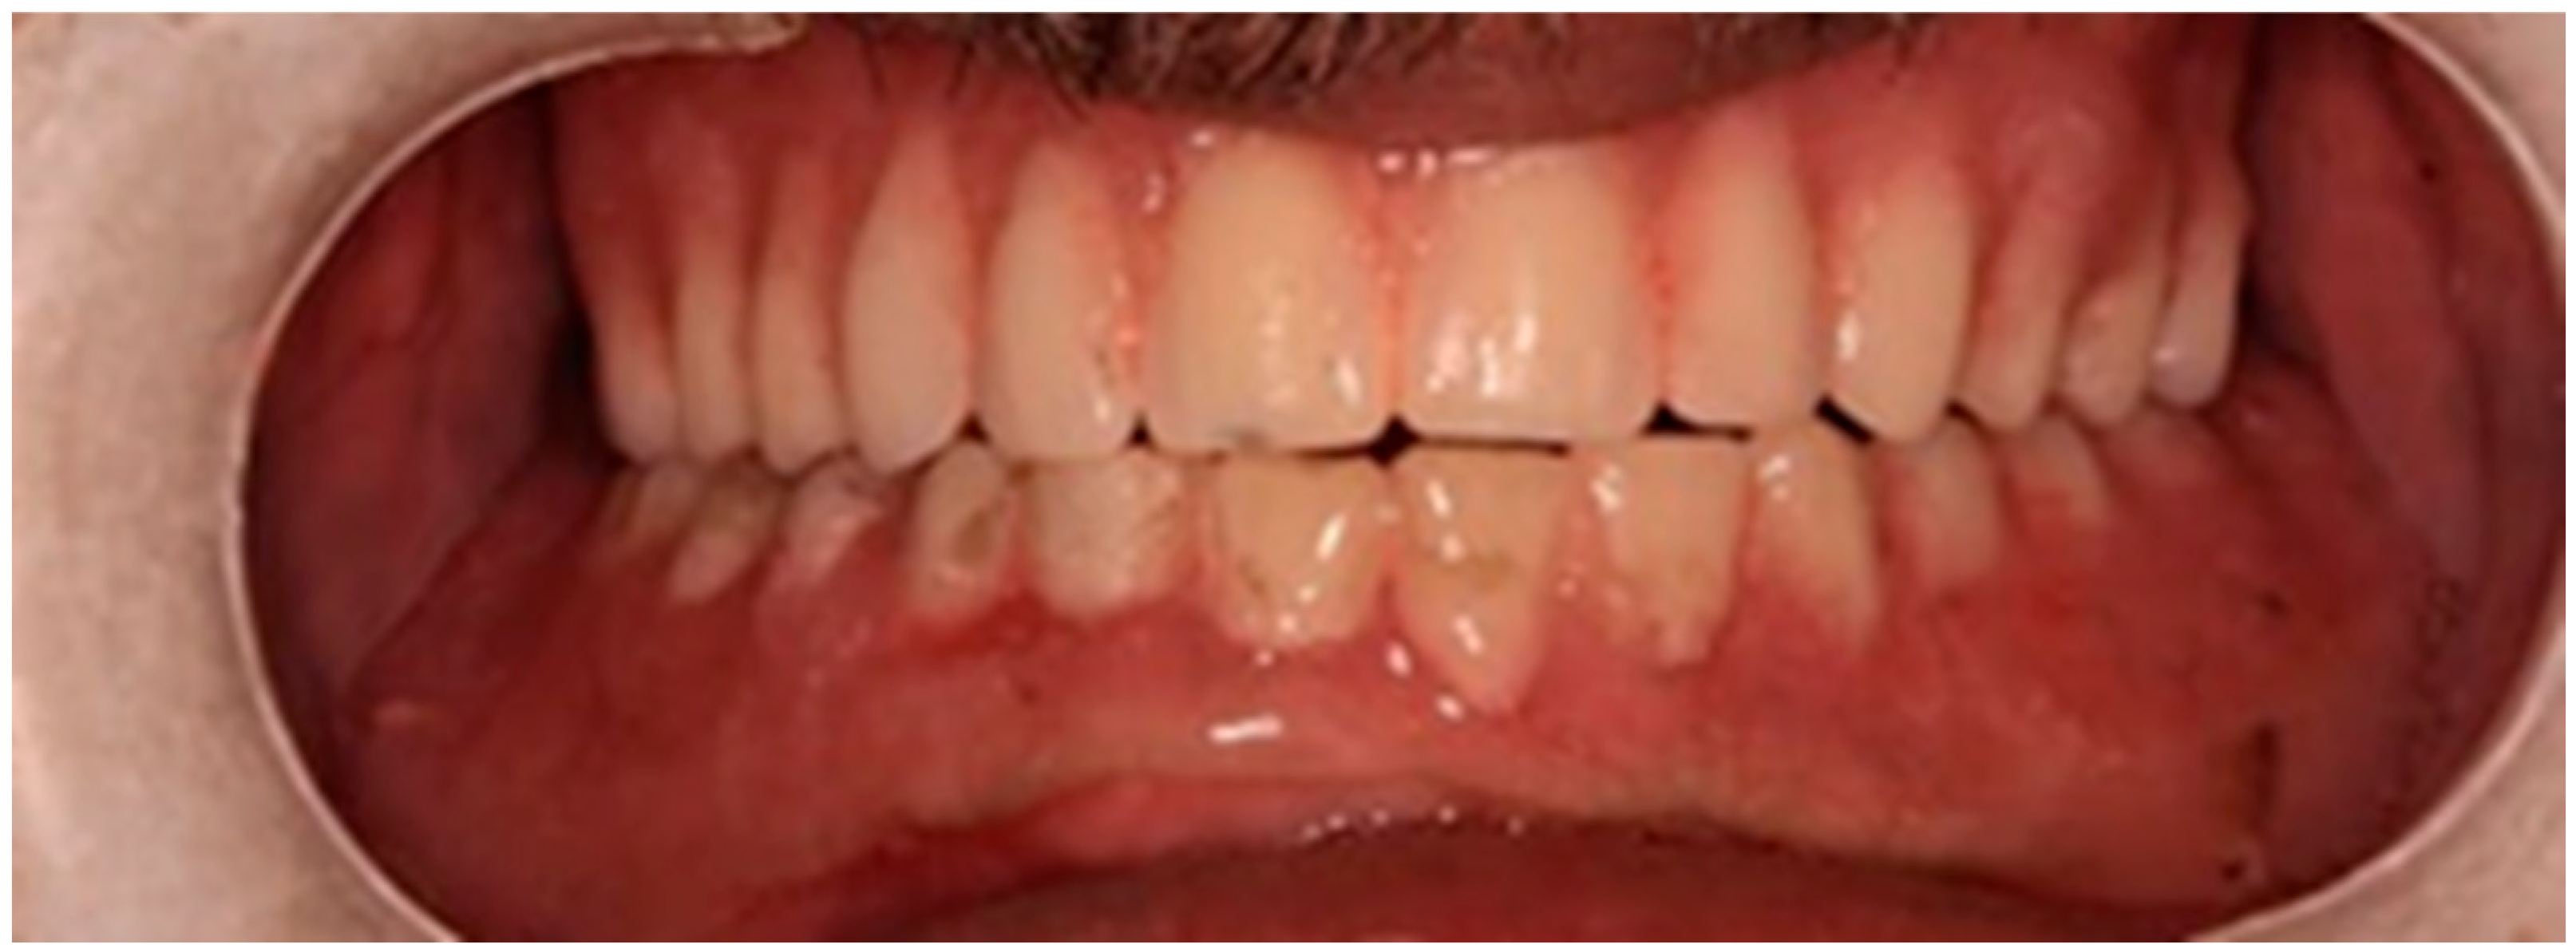

The clinical dental assessment, at the time, indicated a completely edentulous maxilla and a partially edentulous mandible. The residual mandibular teeth exhibited periodontal compromise, classified as Grade 3 mobility according to the Miller Classification, with multiple cavities and a poor overall prognosis (Figure 1).

Figure 1. Preoperative oral condition. (A) The edentulous maxilla. (B) Partially edentulous mandible. (C) Maxillary denture and mandibular partial denture.